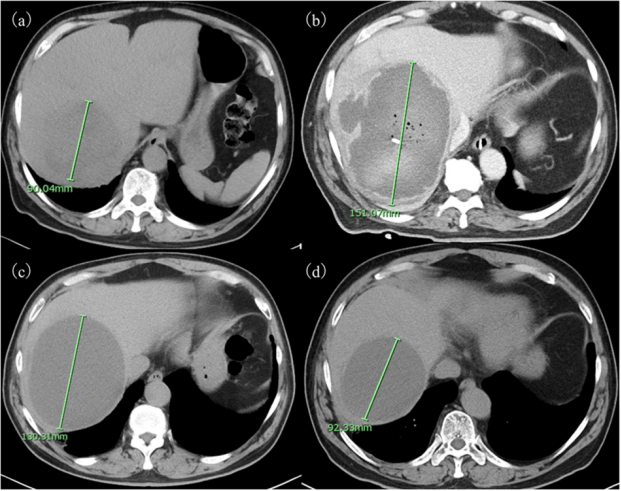

实验室检查显示白细胞增多(白细胞计数,19,100/μl)和血清CRP显著升高(41.4 mg/dl)。腹部CT

显示右肝叶有一处9.0cm的低密度病变(图1a)。临床诊断为肝脓肿后,予以他唑巴坦/哌拉西林

联合甲硝唑治疗,并行经皮肝脓肿引流术,引流出不足100毫升的果酱样液体。至入院第9天,患者病情加重,出现意识改变和严重呼吸衰竭

。CT显示肝脓肿增大至15.1cm,并有病灶内出血(图1b),遂转至我院。

尽管一般状况改善,炎症指标及肝功能检查

恢复正常,但第39天随访CT仍显示13.1cm肝脏病灶。因无法再抽出更多脓液,于第40天拔除引流管

随访期间,患者临床状况及肝功能持续稳定,但CT检查

显示肝脏病灶持续存在:治疗后1年为13.0 cm(图1c),3年时缩小至9.2 cm(图1d)。鉴于病灶体积呈逐渐缩小趋势,遂继续保持密切随访。

图1 本例肝脓肿的腹部CT图像。病程第5天,腹部CT显示右肝叶有一个直径为9.0cm单发病灶(a);第9天,尽管行经皮引流,病变已经迅速扩大到15.1cm(b);一年后,病灶仍较大,为13.0cm(c);治疗后3年,病灶略缩小至9.2cm(d)。